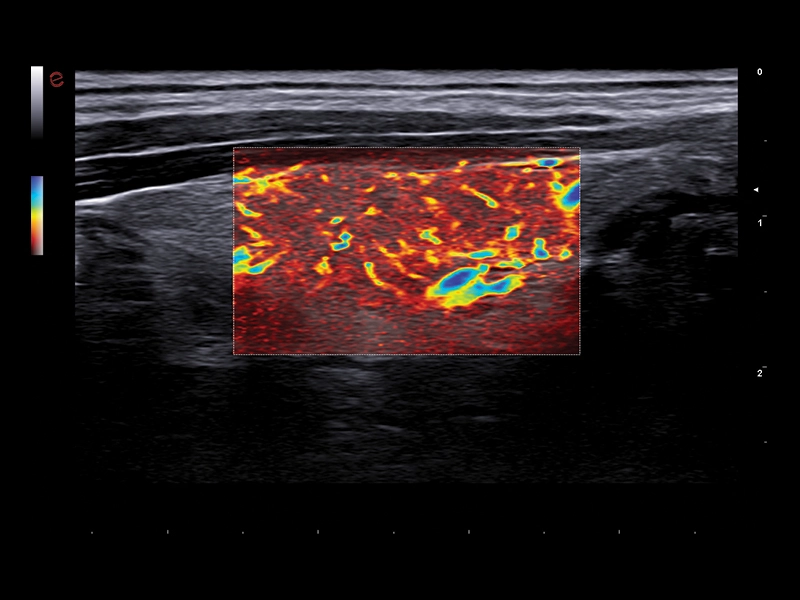

MyLab™9 Platform - Very-superficial linear imaging with Power Doppler algorithm

MyLab™9 Platform - Very-superficial linear imaging with Power Doppler algorithm